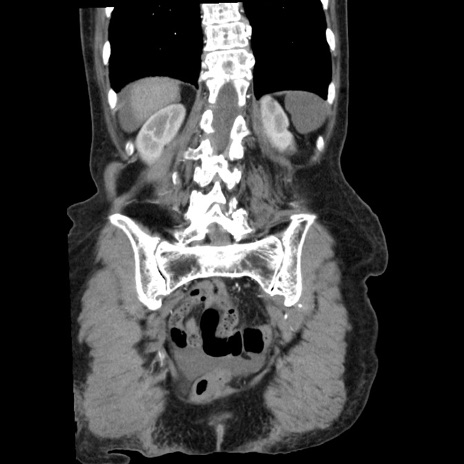

横断像

【症例】80歳代女性

【主訴】腹痛

【現病歴】8時間前から腹痛あり来院。

【既往歴】糖尿病、脂質異常症、子宮体癌にて子宮全摘術

【身体所見】意識清明・会話良好だが腹痛で苦悶様、全腹部にわたって反跳痛と圧痛あり

【データ】WBC 13600、CRP 0.14、LDH 224、CK 90